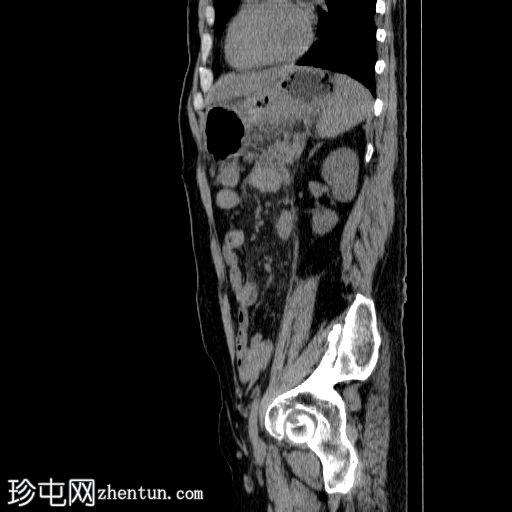

3.jpg

矢状面

非造影

胰体尾弥漫性增大,特征为胰腺实质低强化,无明显坏死区域。

该病灶与以下表现相关:

胰周筋膜平面边界不清的污迹,无明显壁形成、气室、固体碎片或血液产物。

病变横向延伸至左前肾旁间隙,伴有Gerota筋膜增厚。

病变向下延伸至盆腔。

无肠系膜或脾脏血管阻塞的证据。

未见导管扩张或钙化。